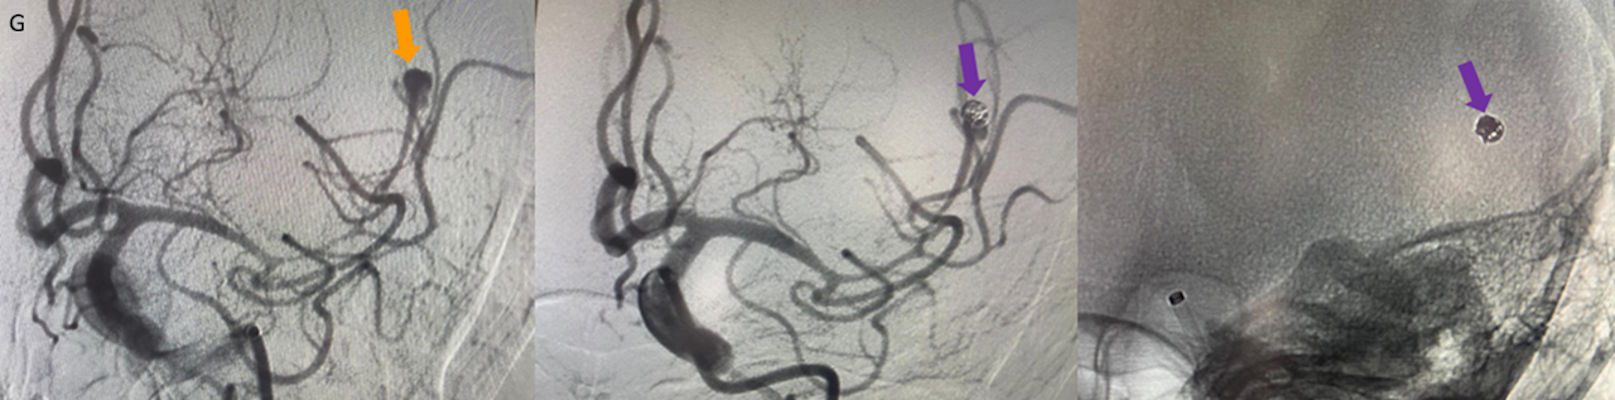

- Kontrastlı T1A görüntüde (C) ve kontrastlı T1A çıkarma görüntüde (D) medialde bulunan alanda kontrastlanma izlenmezken (ok), lateralde bulunan boyutça daha küçük alanda kontrastlanma izleniyor (ok). Ayrıca anevrizma komşuğunda silvian fissürde leptomeningeal kontrastlanma görülüyor.